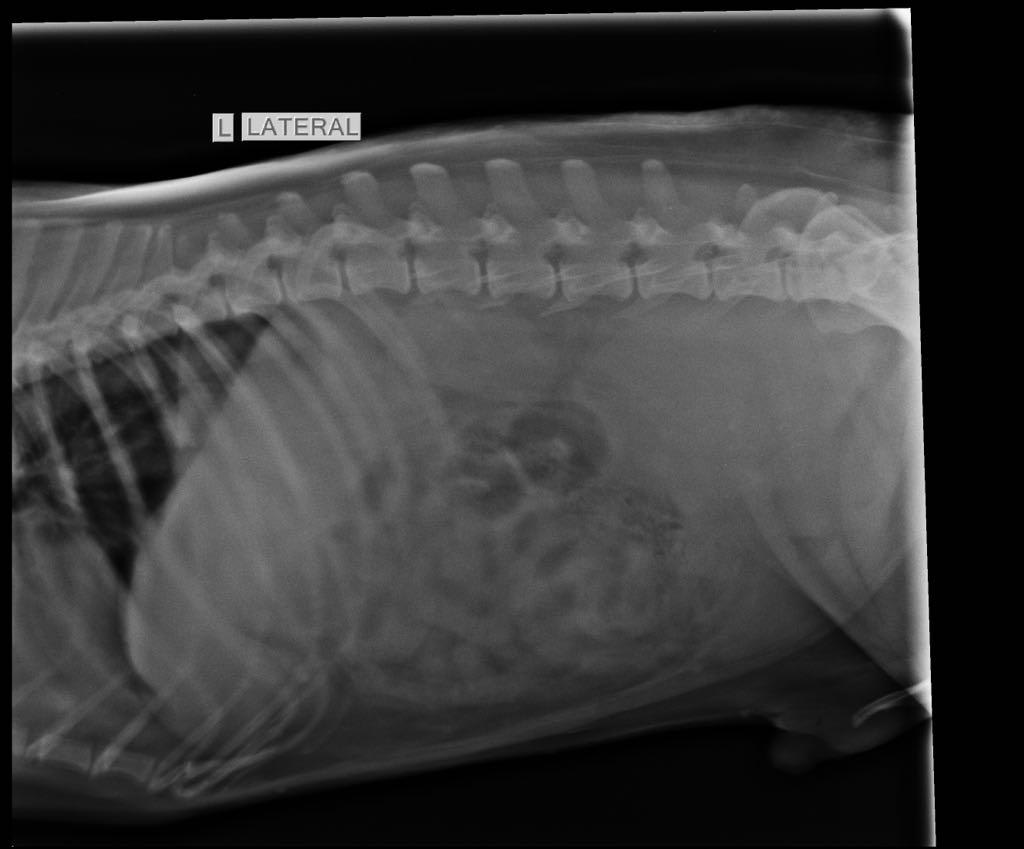

Pet's info: Dog | Mixed Breed | Male | unneutered | 15 years old | 46.5 lbs

Hi, I have a 15year old indie mix breed dog, not neutered been diagnosed with mass in prostrate, biopsy not done. His symptoms limping with hind limb, straining while urinating and passing stool In constant pain around prostate mass and hip bones Vet suggested it’s a 80*88mm tumor and can’t be treated due to surgery so should be put to sleep Please advise as there is no blood in urine and no weight loss yet is there a possibility of that this isn’t tumor and just a mass